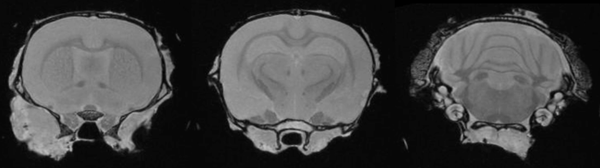

Ex-Vivo Imaging: Ex vivo imaging can produce high-resolution images of the rat brain, providing excellent delineation of brain regions. Image Credit: Scintica Instrumentation Inc

Ex vivo imaging can produce high-resolution images of the rat brain providing excellent delineation of brain regions. Image Credit: Scintica Instrumentation Inc